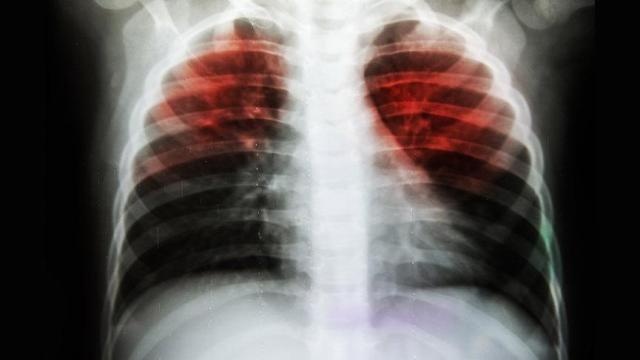

Tüberküloz, Kronik Viral Hepatitler, lösemi, anemi,

astım, kronik solunum yetmezliği, toksik karaciğer hastalığı,